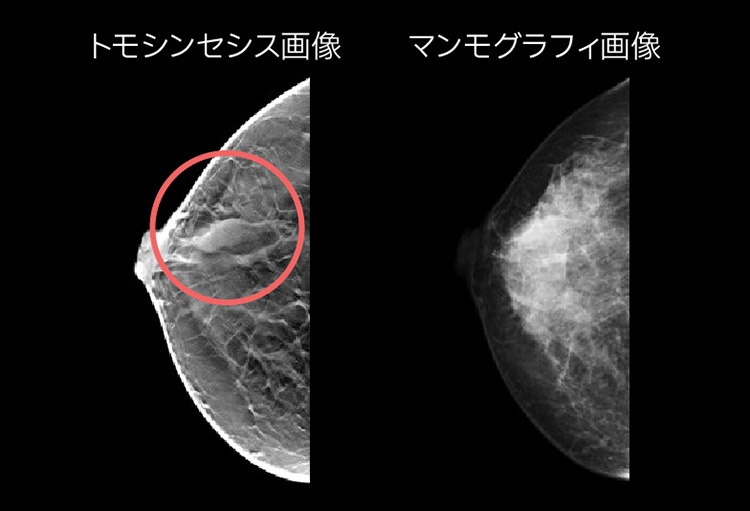

マンモグラフィは、乳腺組織を見やすくするために乳房を薄く広げながら圧迫して撮影します。しこりとして触れないごく早期の乳がんなど、乳房に出来る病気を見つけることが出来ます。当院では2016年3月より、「トモシンセシス」という断層撮影のできる新装置を導入いたしました。この撮影では、角度を変えて複数の方向から乳房を撮影し、乳房を1mmごと輪切りにスライスして写すことが出来ます。若年の方など乳腺の多い方は、通常のマンモグラフィを撮影しても乳腺が真っ白に写り、病気が見つけづらいことや、乳腺の重なりが病気に見えてしまうこともありました。しかし、トモシンセシス撮影で乳房を薄くスライスすることにより、病気と乳腺の重なりを分離し、より正確な診断が期待できます。さらに最新の技術により、従来の装置よりも被ばく線量が30%低減されました。出来るだけリラックスして検査を受けて頂けますよう、新装置には優しく光るイルミネーション機能を搭載し、検査室にはオルゴールの音楽を流して少しでも安らげる環境を心がけております。